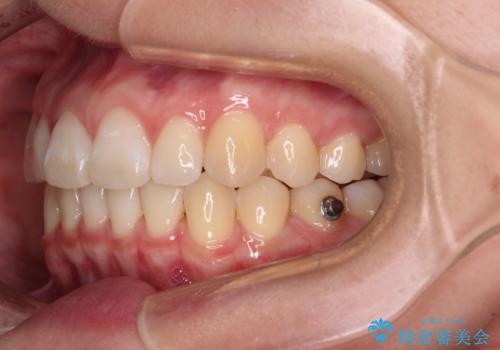

- 上顎前歯の隙間を気にして来院された患者様です。

下顎前歯が上顎前歯に食い込むような咬み合わせにより、上顎前歯が開いてしまっていたため、咬合高径の挙上により突き上げを改善するよう、インビザラインにより矯正治療を行うこととしました。

咬合高径の挙上により上顎前歯の突出感も改善することができ、整った口元となりました。